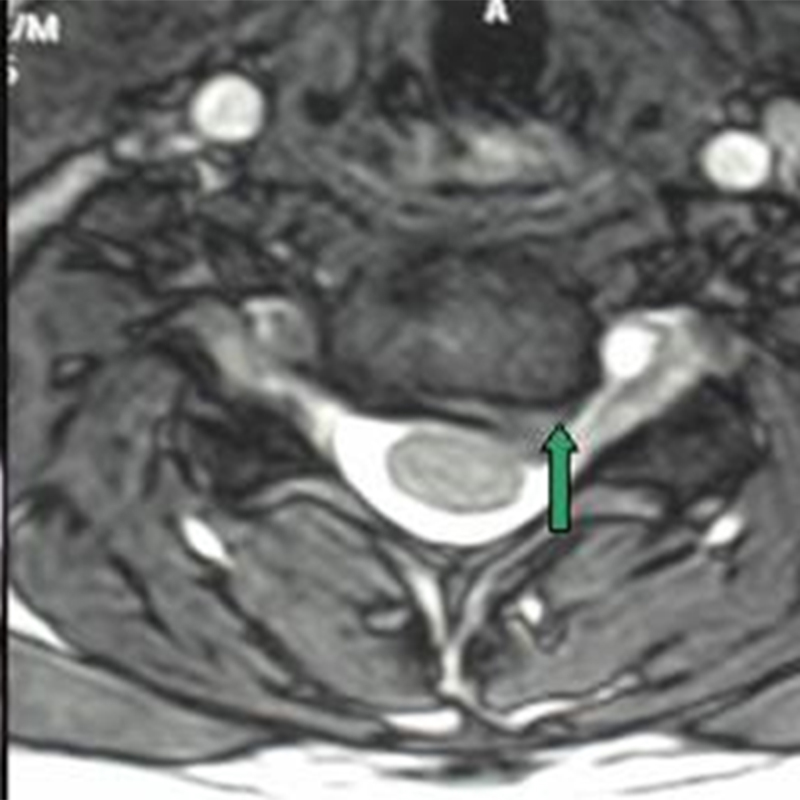

Mục tiêu Việc sử dụng vancomycin bột trong phẫu thuật cột sống để phòng nhiễm khuẩn vết mổ đã được thảo luận nhiều trong y văn. Nhiều nghiên cứu cho thấy sử dụng vancomycin bột tại chổ có hiệu quả giảm tỷ lệ nhiễm trùng sau mổ nhưng một số nghiên cứu khác lại cho thấy việc này không có hiệu quả. Hiệu quả của vancomycin trong giảm tỷ lệ […]